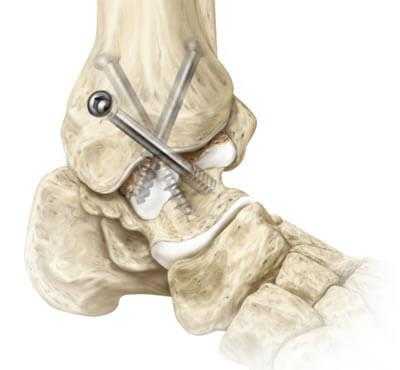

Обездвиживание достигается за счет жесткого соединения примыкающих концов костей сустава между собой специальными металлическими фиксаторами: спицами, винтами, штифтами. Это позволяет суставным поверхностям срастись друг с другом под нужным углом, то есть привести сочленение в полное неподвижное состояние, что снимает болевой синдром.

1. Внутрисуставный. Вскрытие капсулы сустава с последующим удалением поврежденного гиалинового хряща с поверхностей костных элементов. После репозиции костей в выгодном положении выполняется их фиксация металлическими приспособлениями.

3. Комбинированный. Сочетание в одном хирургическом процессе внутрисуставного и внесуставного способов. Хрящевые структуры с сустава полностью счищаются, внедряется аутотрансплантат, который фиксируется специальными металлическими пластинами.

4. Компрессионный. Сдавливание сочленяющихся поверхностей аппаратом компрессионного или компрессионно-дистракционного типа для дальнейшего их сращения. Применяются аппараты Илизарова, Гришина, Волкова-Оганесяна. Удаление хряща не исключается. Вживление костного трансплантата для способа компрессии не требуется.

- Внутрисуставный. В процессе хирургии выполняется вскрытие капсулы сустава с последующим удалением поврежденного гиалинового хряща с поверхностей костных элементов. После репозиции костей в выгодном положении выполняется их фиксация металлическими приспособлениями.

- Комбинированный. Эта техника подразумевает сочетание в одном хирургическом процессе двух способов: внутрисуставного и внесуставного. Так, хрящевые структуры с сустава полностью счищаются, внедряется аутотрансплантат, который фиксируют специальными металлическими пластинами.

- Компрессионный. Операция заключается в сдавливании сочленяющихся поверхностей аппаратом компрессионного или компрессионно-дистракционного типа для дальнейшего их сращения. Широко применяемые конструкции - аппараты Илизарова, Гришина, Волкова-Оганесяна. Удаление хряща не исключается. Вживление костного трансплантата для способа компрессии не требуется.

- Дальше стопа выводится из порочного положения. Большеберцовый элемент и таранный компонент плотно сопоставляют друг с другом в удобной с точки зрения физиологии позиции. Достигнутая позиция скрепляется металлической конструкцией необходимого типа.

- Используемые операционные ходы на завершающем этапе закрывают при помощи послойного ушивания мягких тканей с оставлением дренажа.

Артродез голеностопного сустава может проводиться как под общей анестезией, так и при спинальной анестезии (обезболивающие препараты вводятся в позвоночник, нижняя часть тела не воспринимает болевых ощущений). В ходе проведения операции врач производит разрез и резецирует сустав. Иногда для сращивания костей врачи используют специальные медицинские винты, шурупы, стальные пластины, стальные стержни или костные трансплантаты. Операция занимает 2 часа, в зависимости от каждого конкретного случая.